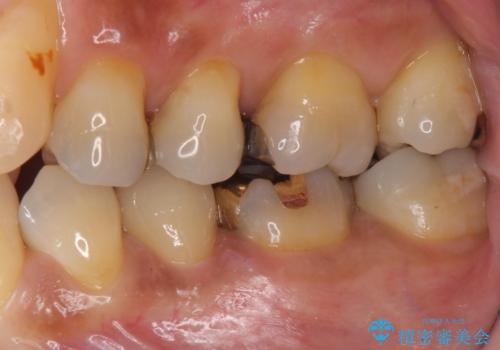

- 左下の奥歯に虫歯がある気がするとのことで来院された患者様です。

手前はジルコニアクラウンで白く、奥はゴールドアンレーでより適合の良いものを装着します。

銀歯の裏側に虫歯が確認されました。

小さな段差も虫歯のリスクにつながります。

精度の良い補綴物を入れることで今後の虫歯リスクを抑えることができます。